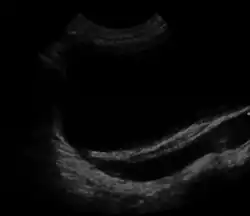

![]() | |

| Ultrasound image showing abnormal vesicoureteral junction and dilated distal ureter resulting in primary vesicoureteral reflux (VUR). | |